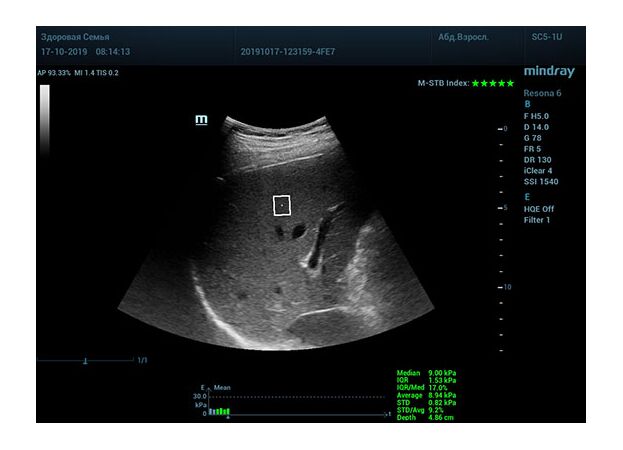

Определение плотности печени. Не ошибся ли оператор при измерении эластических свойств печени? Для оценки критериев качества предусмотрен индекс MBT, который покажет насколько «твердой» была рука оператора и двигалась ли печень. При MBT 5* рука тверда и показатели достоверны. Для оценки качества результатов используется IQR индекс, отображающий колебания показателей в точке измерения при расчете медианы. Показатели при IQR <30% считаются приемлемыми. Техника сканирования через межреберные промежутки требует размещение окна интереса на несколько сантиметром ниже капсулы, для исключения эффекта реверберации. Установка ROI на паренхиму без захвата сосудов, для исключения погрешностей измерения.

Стадия фиброза определяется по системе METAVIR Staging, построенной на данных биопсии и сопоставлении с данными эластографии. Своевременная диагностика фиброза, и начало его лечения, залог благоприятного исхода заболевания.

• METAVIRF2 – Портальный фиброз с вовлечением нескольких перегородок